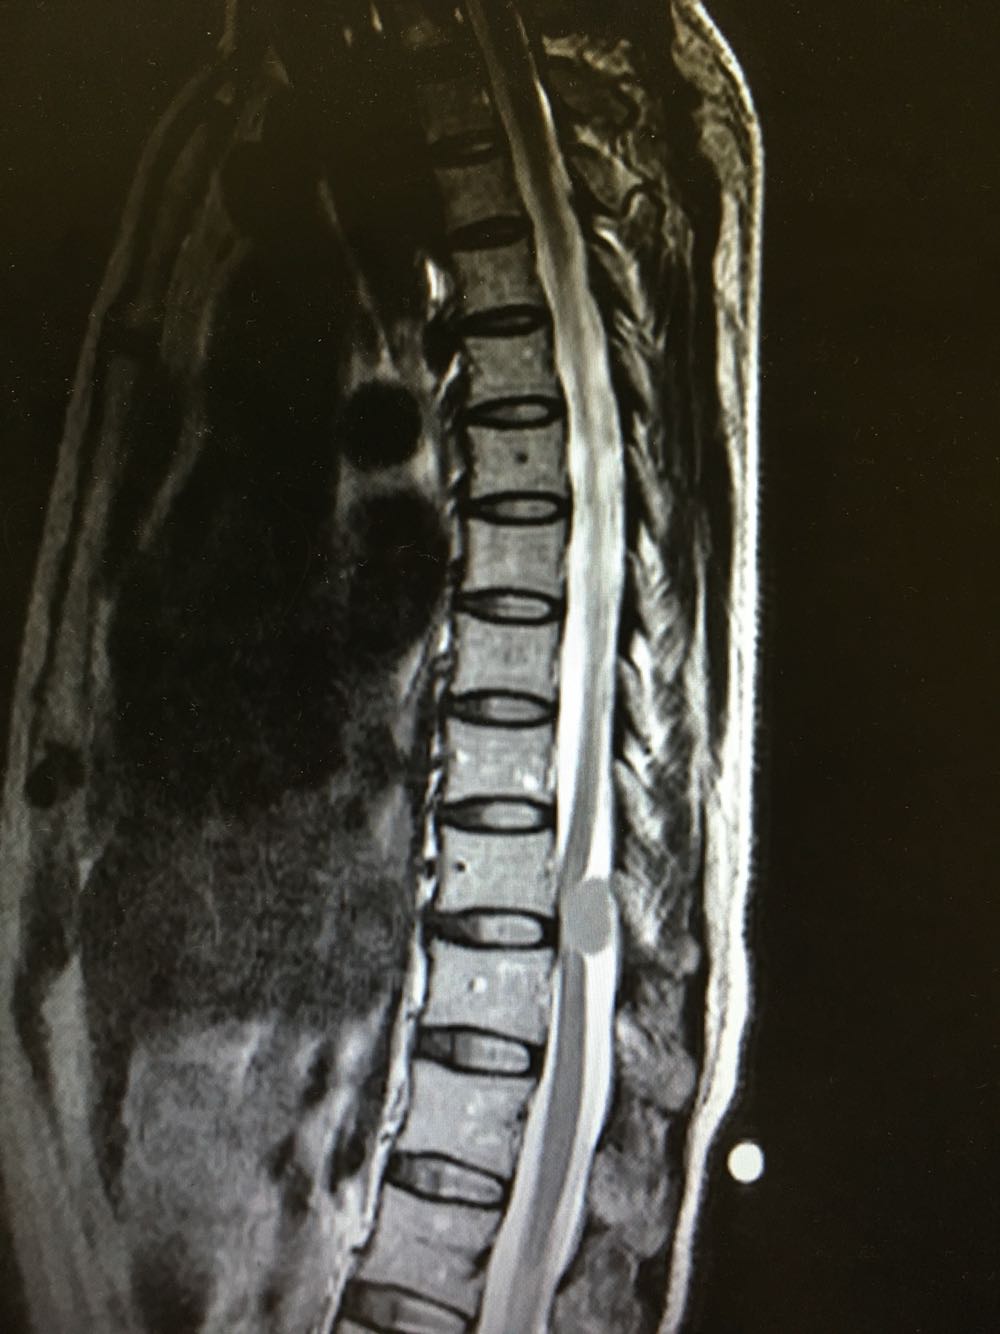

患者,女性,44岁 主诉:进行性双下肢麻木无力1年余 现病史:患者1年前自觉腰痛及脚底脚背麻木不适,至当地医院就诊考虑:腰椎间盘突出,予推拿及针灸治疗,未见明显缓解,症状时有加重,近1周上述症状加重明显,遂至我院就诊,查MR示:T10-11处混杂信号,考虑肿瘤可能,现为进一步诊治收治入院,发病以来,神清,精神可,胃纳夜眠可,二便无殊,体重无明显变化。

查体:左下肢肌力V级,右侧下肢肌力IV级,肌张力正常,膝反射亢进,病理反射未引出,双下肢感觉较差。 辅检:见现病史

诊断:脊髓肿瘤(T10-T11) 治疗:完善术前检查行手术治疗